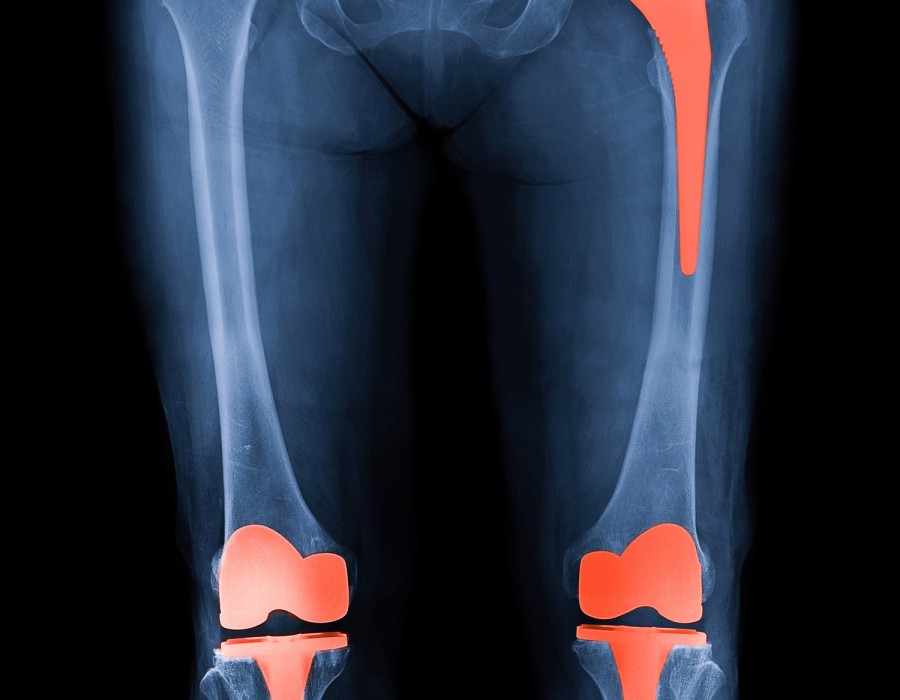

Knee replacement surgery, also known as knee arthroplasty, is a common procedure performed to alleviate severe knee pain and restore function in individuals with damaged knee joints. Knee Replacement Surgeon in Jagatpura, Jaipur This surgery involves replacing the worn-out or diseased parts of the knee joint with artificial implants made of metal alloys, high-grade plastics, and polymers.

Modern advancements in materials and surgical techniques have significantly extended the lifespan of knee replacements. On average, a well-performed knee replacement can last 15 to 20 years or more.Knee Replacement Surgeon in Jagatpura, Jaipur This duration can vary depending on several factors: